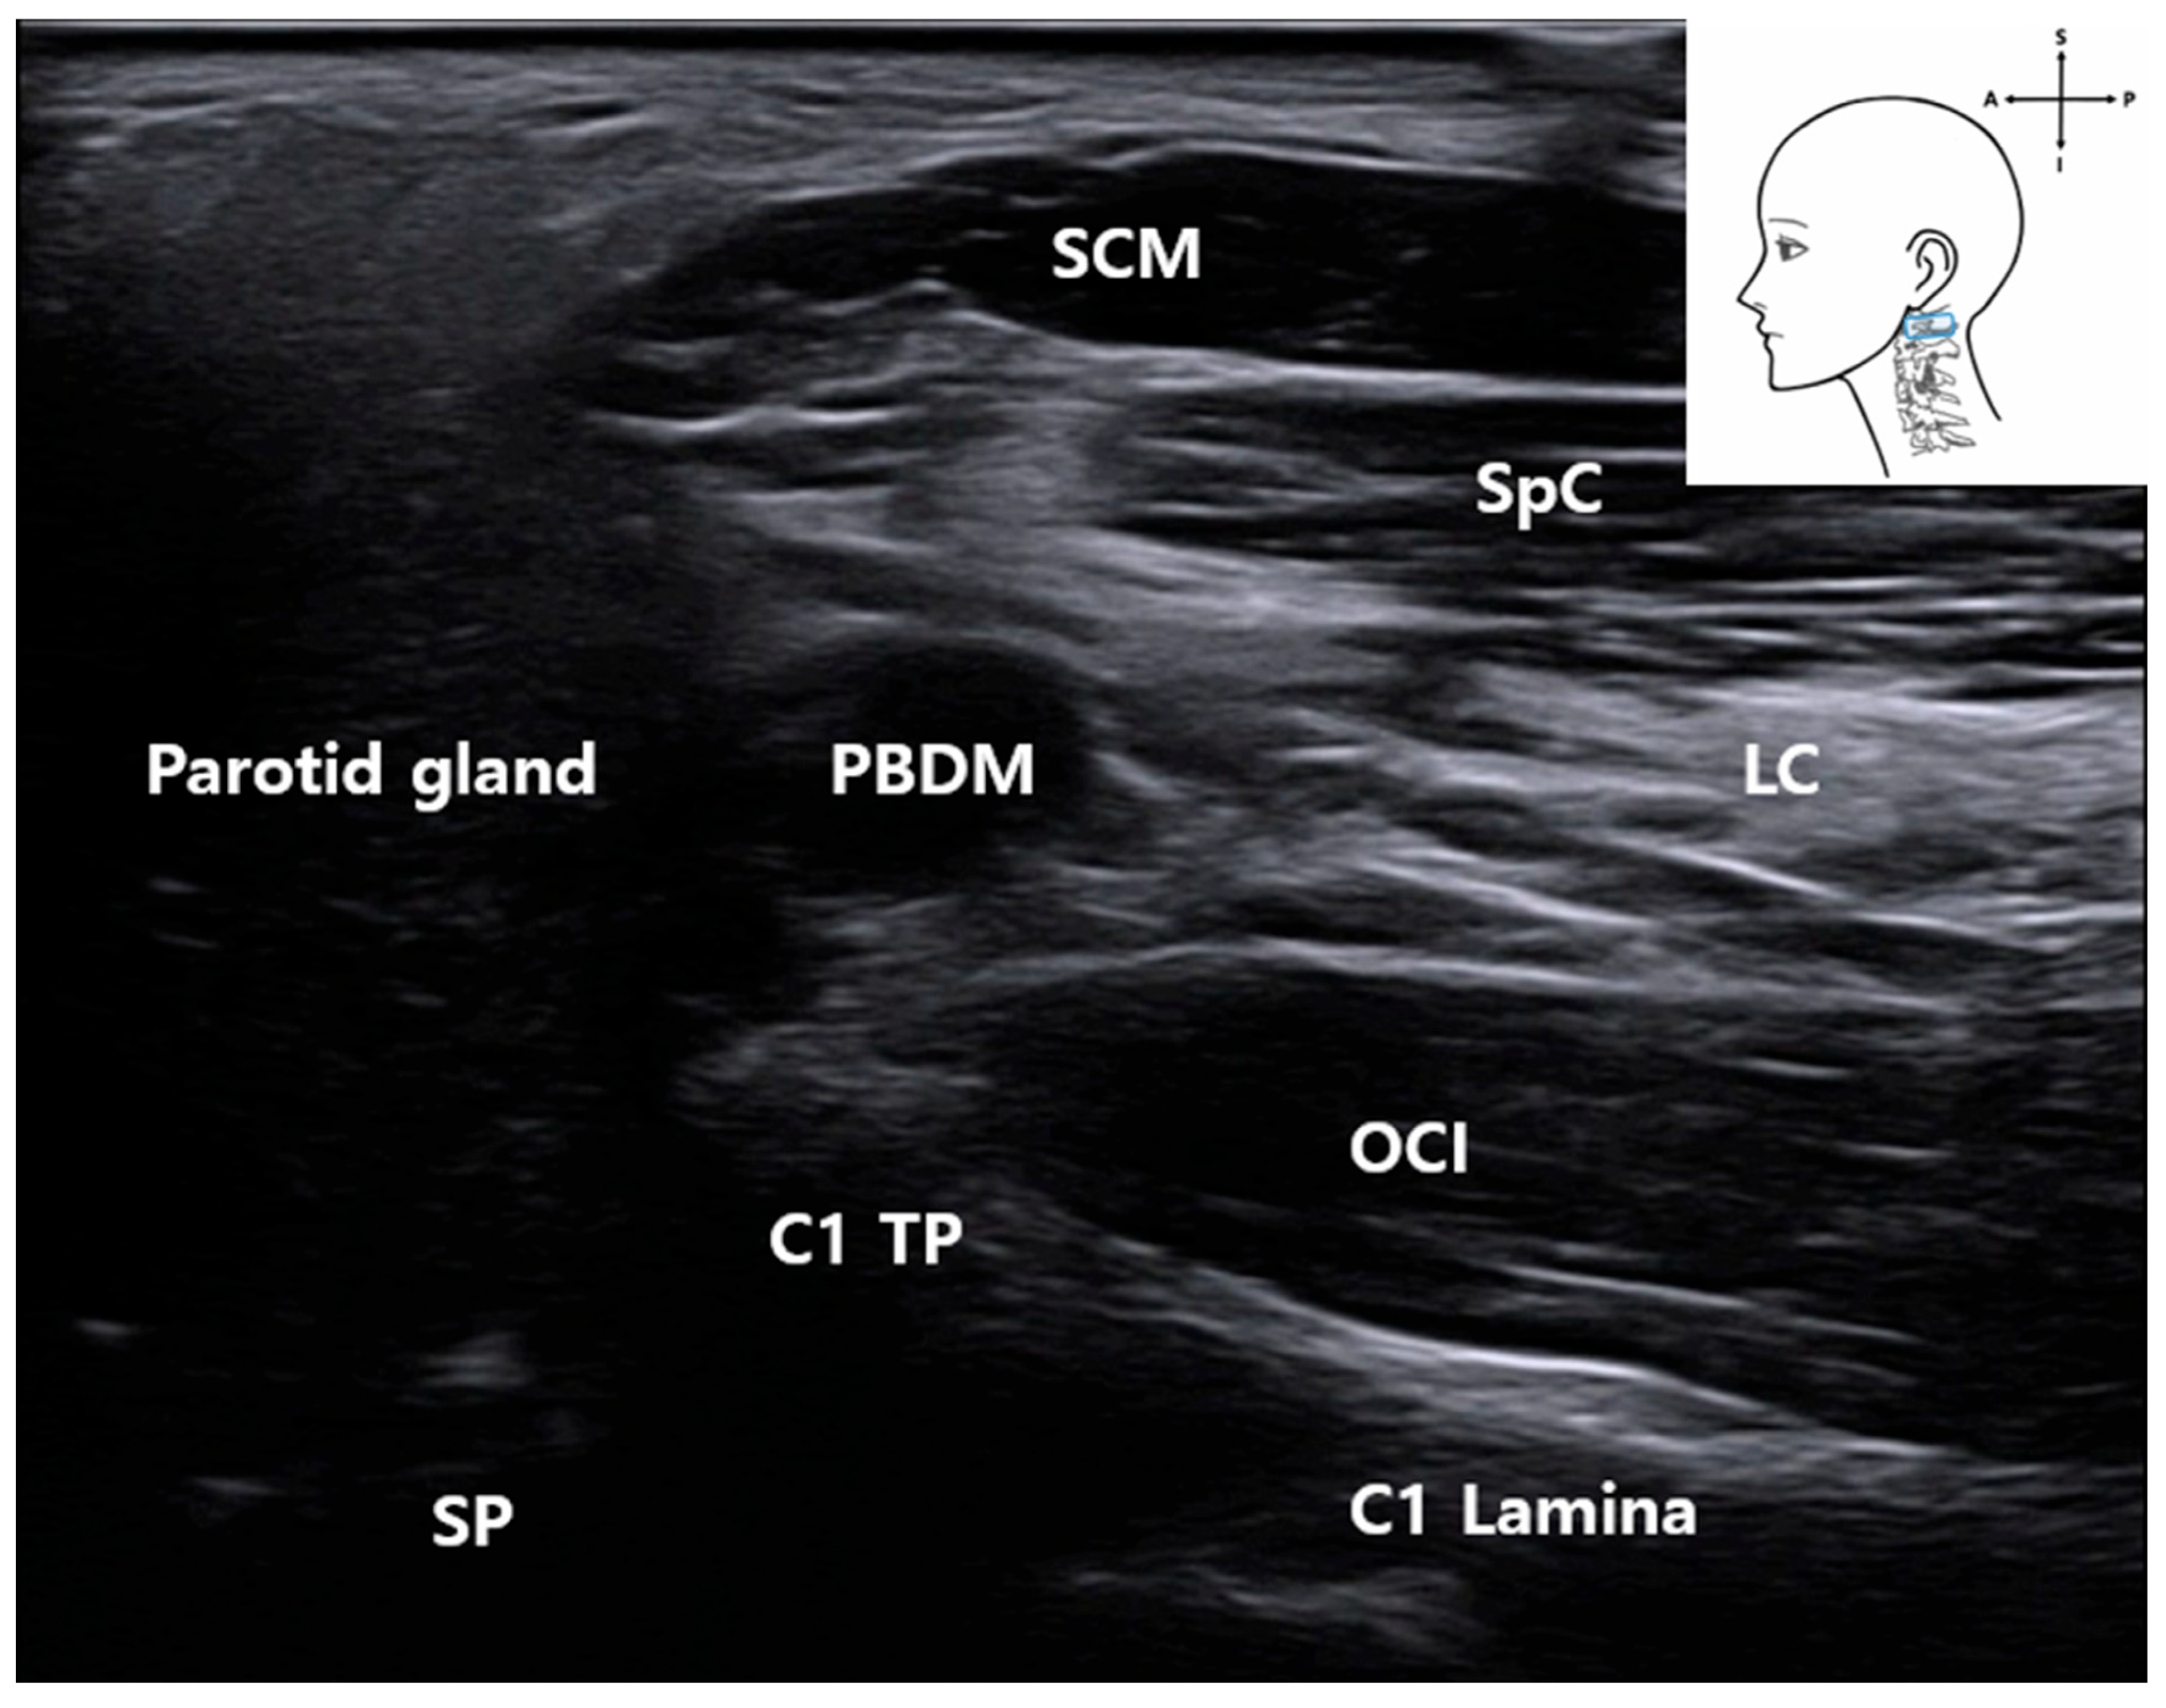

3.3. C1 Detection and Muscles